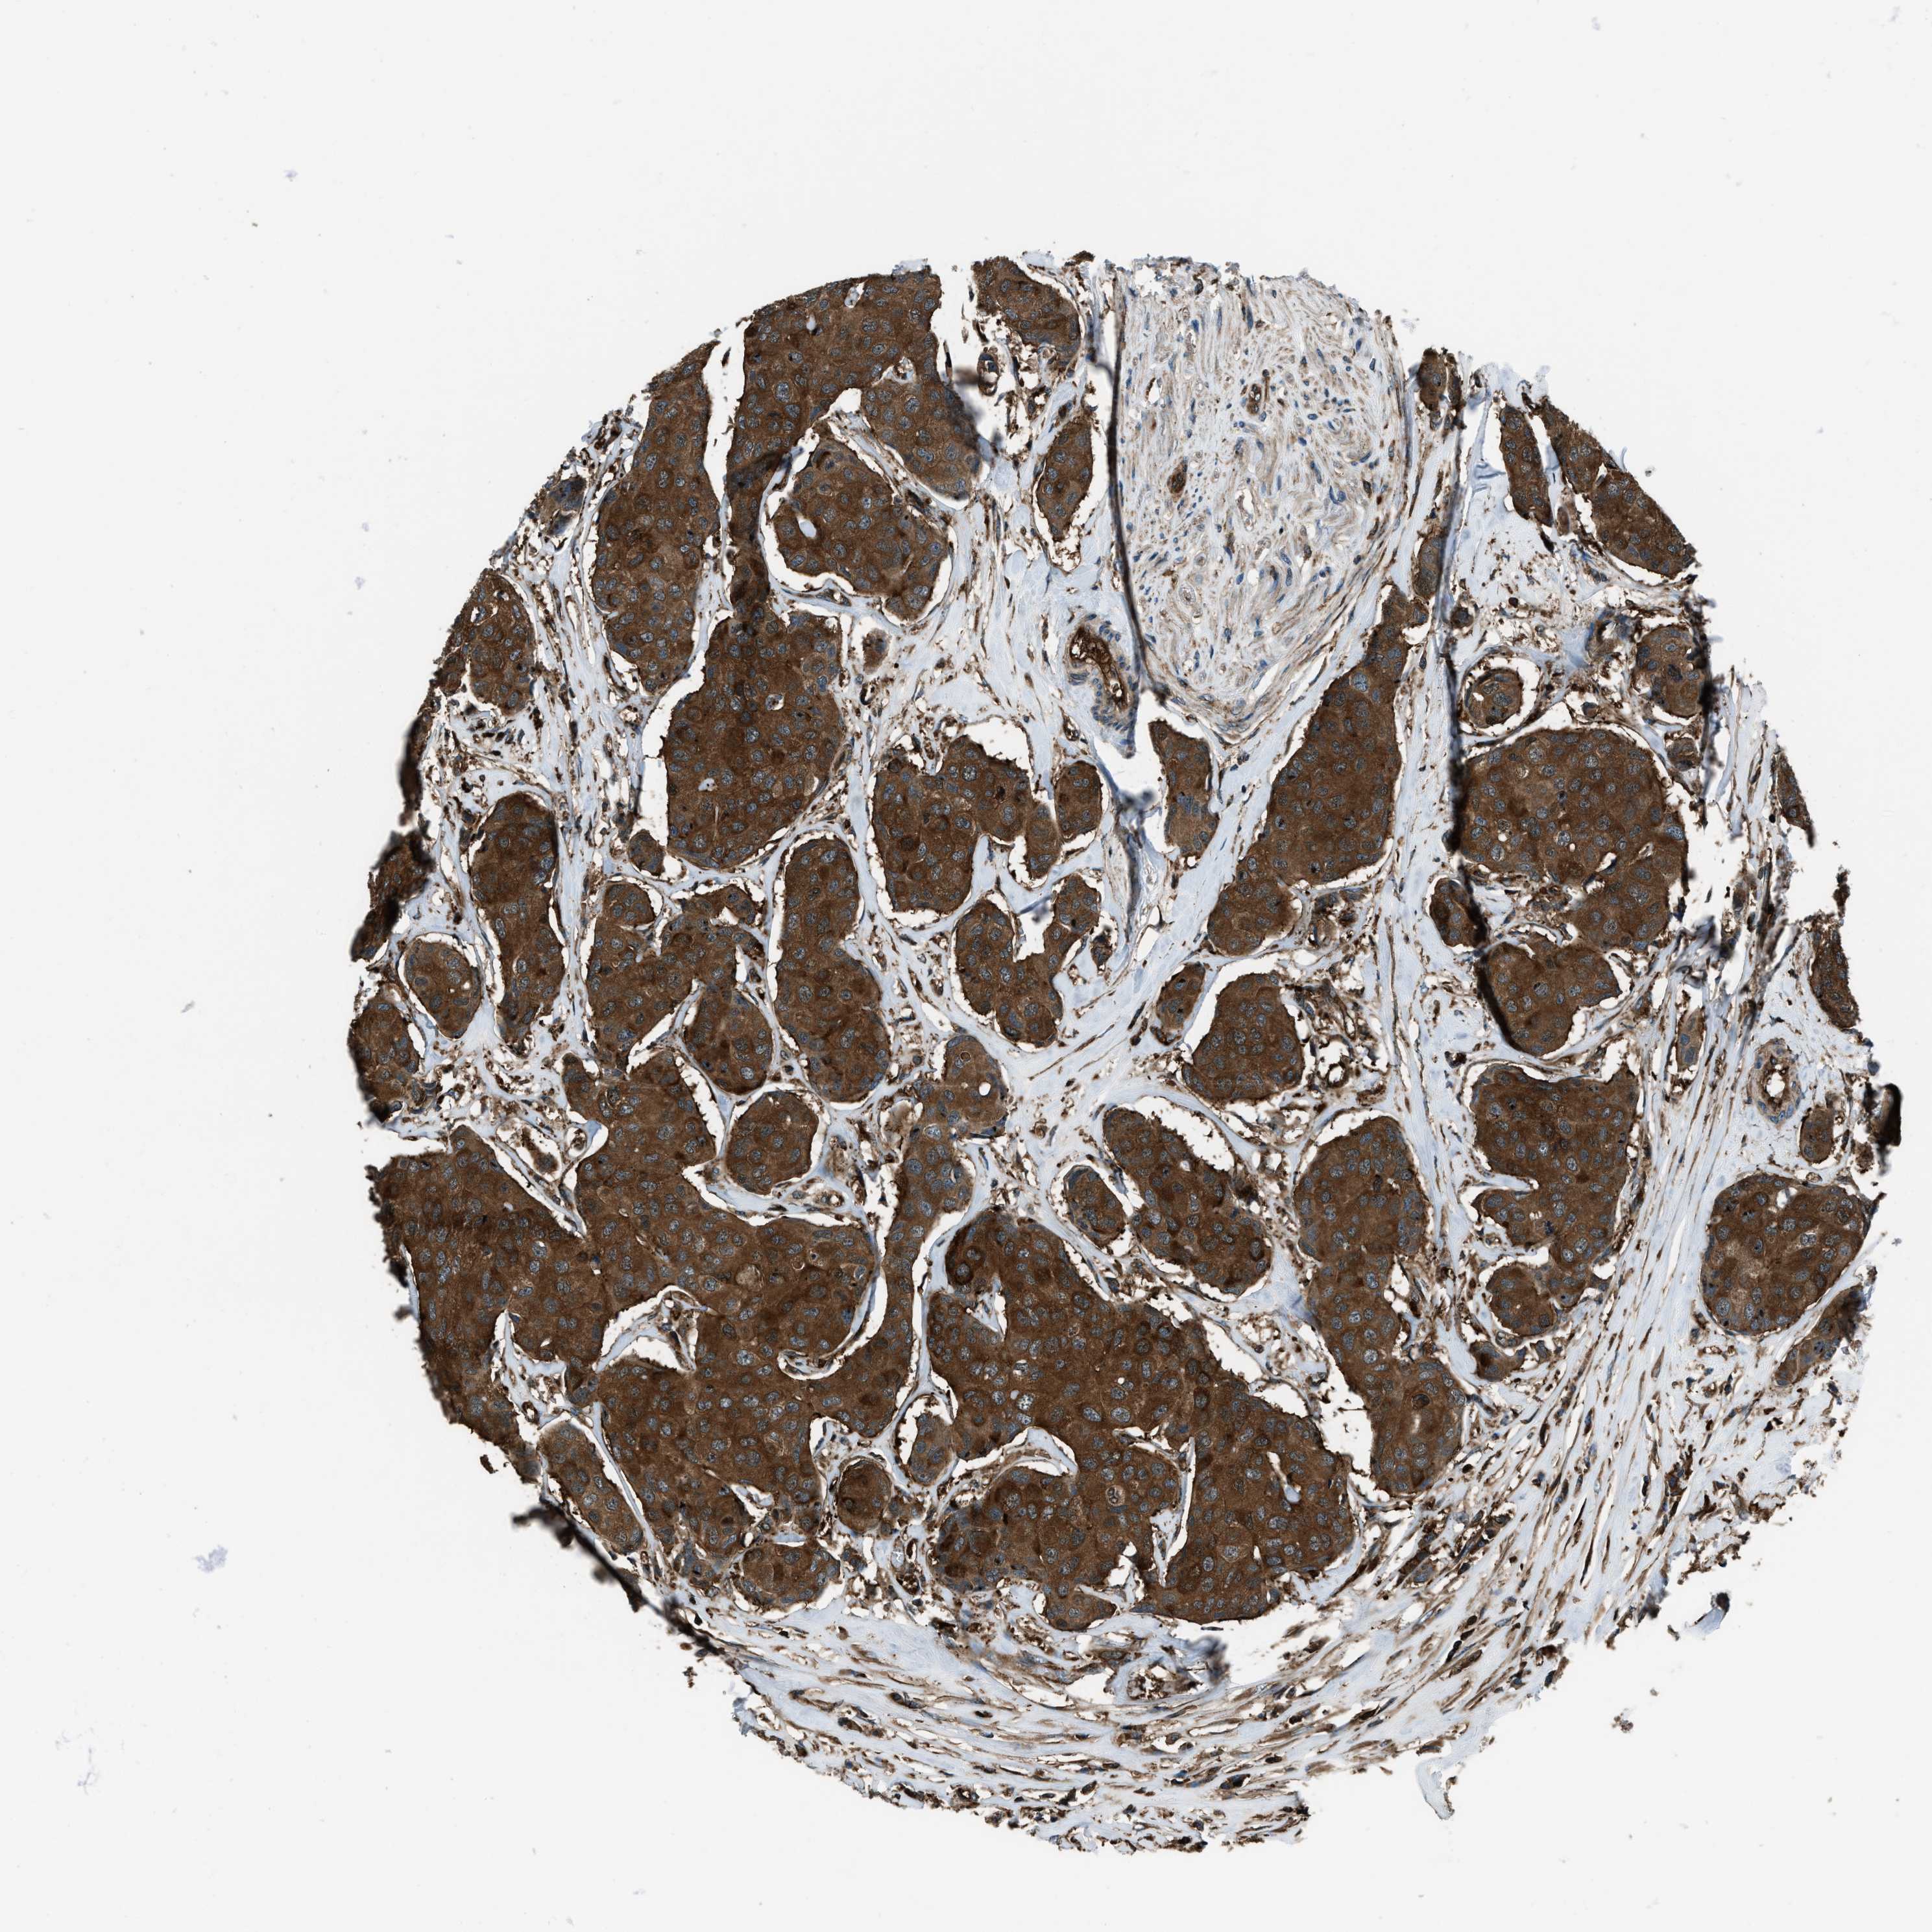

CANCER BREAST CANCER Show tissue menu

BRCA TCGA BRCA VALIDATION PROTEIN EXPRESSION